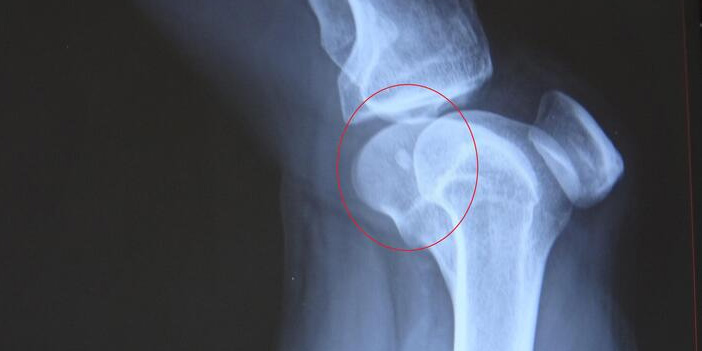

Çağlar, sağ bacağının diz kısmına mermi isabet ettiğini fark etti. Yakınları tarafından Karadeniz Teknik Üniversitesi (KTÜ) Tıp Fakültesi Farabi Hastanesi’ne götürülen Çağlar, tedavi altına alındı.

Çağlar'ın diz kapağındaki mermi ameliyatla çıkartıldı. Mermi balistik incelemeye alınırken, jandarma ekipleri silahı ateşleyen kişiyi tespit etmek için çalışma başlattı.